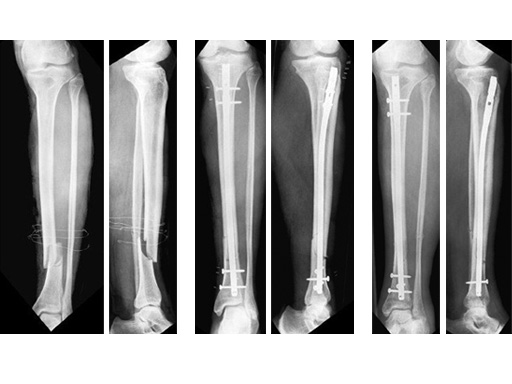

47-year-old man with closed 42-C3 fracture following a sports accident treated with ETNS.